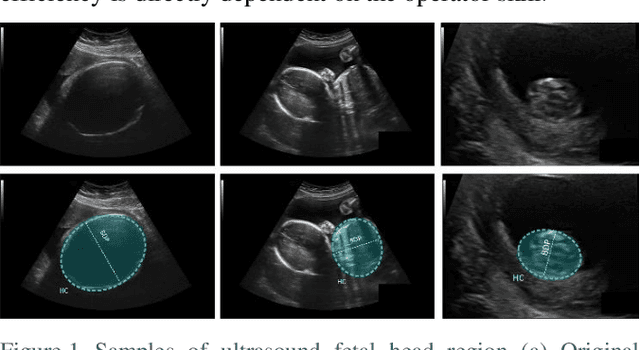

One of the routine examinations that are used for prenatal care in many countries is ultrasound imaging. This procedure provides various information about fetus health and development, the progress of the pregnancy and, the baby's due date. Some of the biometric parameters of the fetus, like fetal head circumference (HC), must be measured to check the fetus's health and growth. In this paper, we investigated the effects of using multi-scale inputs in the network. We also propose a light convolutional neural network for automatic HC measurement. Experimental results on an ultrasound dataset of the fetus in different trimesters of pregnancy show that the segmentation accuracy and HC evaluations performed by a light convolutional neural network are comparable to deep convolutional neural networks. The proposed network has fewer parameters and requires less training time.